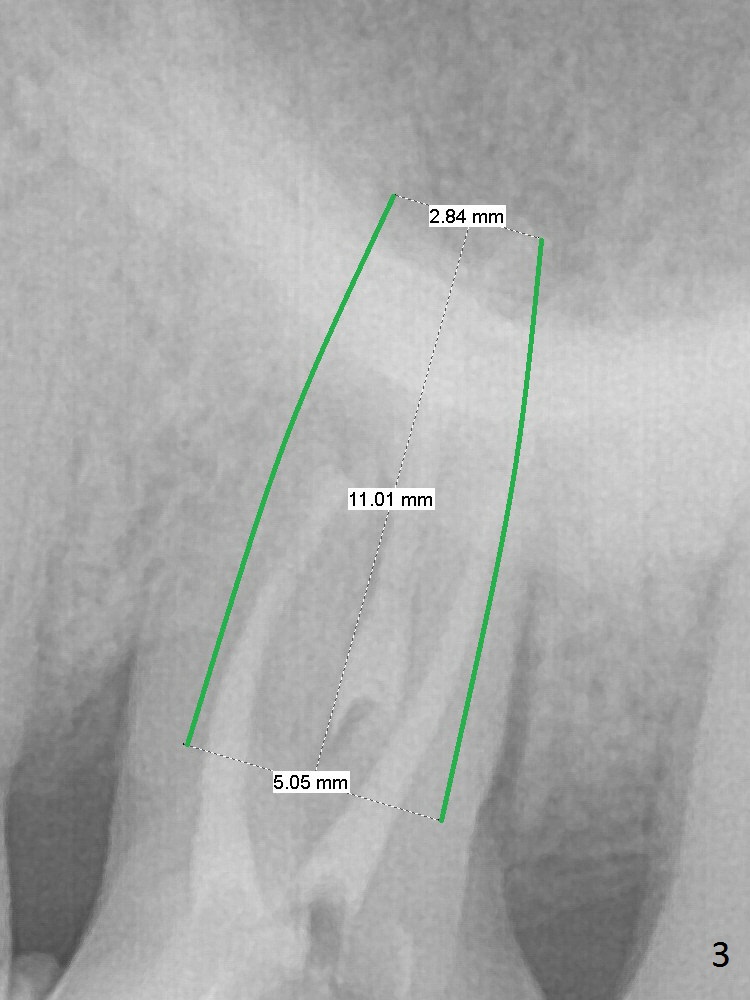

A 70-year-old woman has pain at MB root area post RCT at #14 (Fig.1,2). The tooth seems to have endo-perio disease (bone loss with gingival recession at MB) and be non-salvageable. After extraction and Metronidazole treatment, start osteotomy with 1.6 mm drill 1-2 mm shy of the sinus floor, followed by PA. Use Lindamann bur for ostetoomy position and trajectory adjustment. Use Marking Bur if necessary before Magic Drill 4.3 mm if the septum is wide. The depth of the osteotomy is 1-2 mm coronal to the sinus floor. Do not use the final drill, i.e., saving the osteotomy plug in place. Next 4.5x11 mm dummy implant is placed to push the plug upward for lifting. Place an implant as large as possible, but not violating the buccal gap (Fig.3).